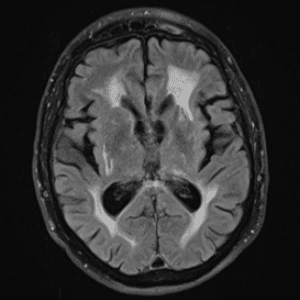

Neurodegenerative Diseases